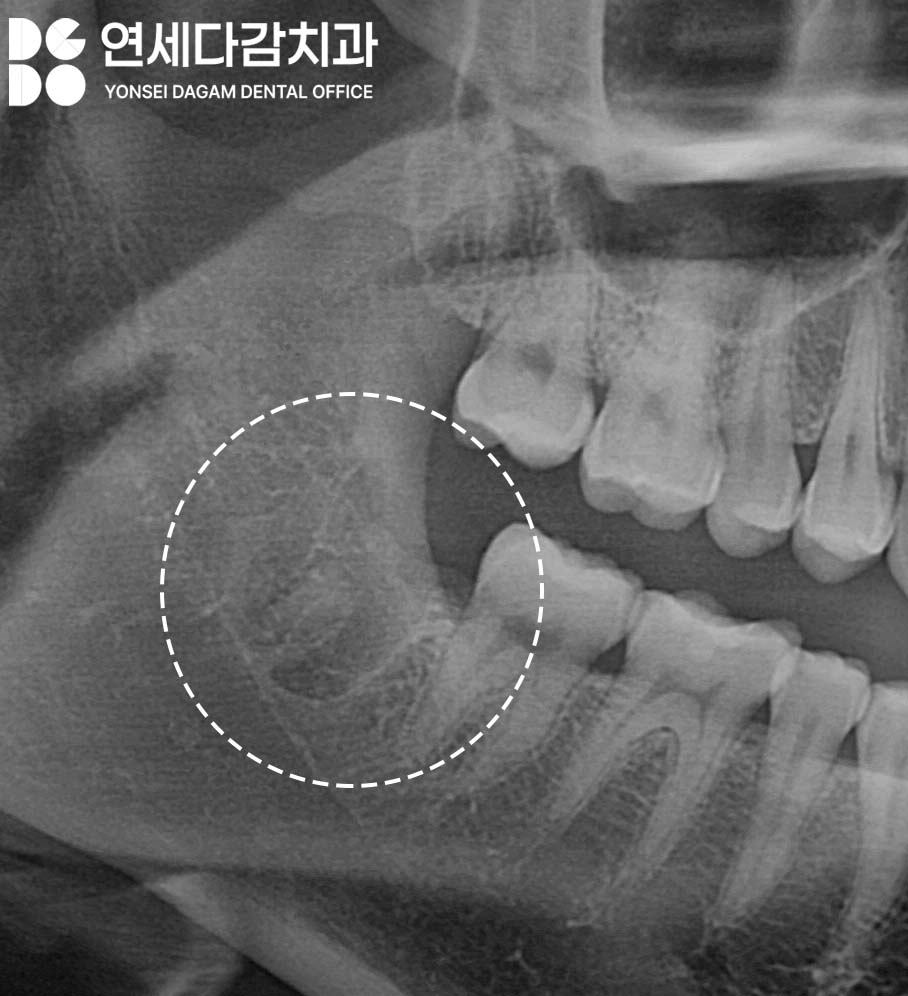

뼈 속에 뿌리 조각이 남아있어도

괜찮을까?

치근이 부러졌다고 해서

항상 이를 모두 제거해야

되는 것은 아닙니다.

거여동 치과 에서도

해부학적 위치 분석과

과거 병력 조사를 통해

안전한 방향으로 접근합니다.

뼈 속에 남아 있는 작은 치근 조각은

대부분 문제가 되지 않습니다.

2~3mm 정도의 조각은

염증이 없던 치아였다면

주변 뼈가 서서히 메우는 과정에서

자연스럽게 흡수되거나

별다른 증상을 일으키지 않고

지내는 경우가 많죠.

따라서 거여동 치과 에서

보여드린 사진들처럼

다각도로 영상을 분석하고

병력을 확인한 뒤

판단하게 되는 것이죠.

문제는 잔존치근이

설하간극과 가까운 경우입니다

설하간극은 혀 아래쪽 공간으로

부드러운 연조직으로 이루어져 있어

치근이 이곳으로 빠지면

위치가 이동하며 제거가 어렵습니다.